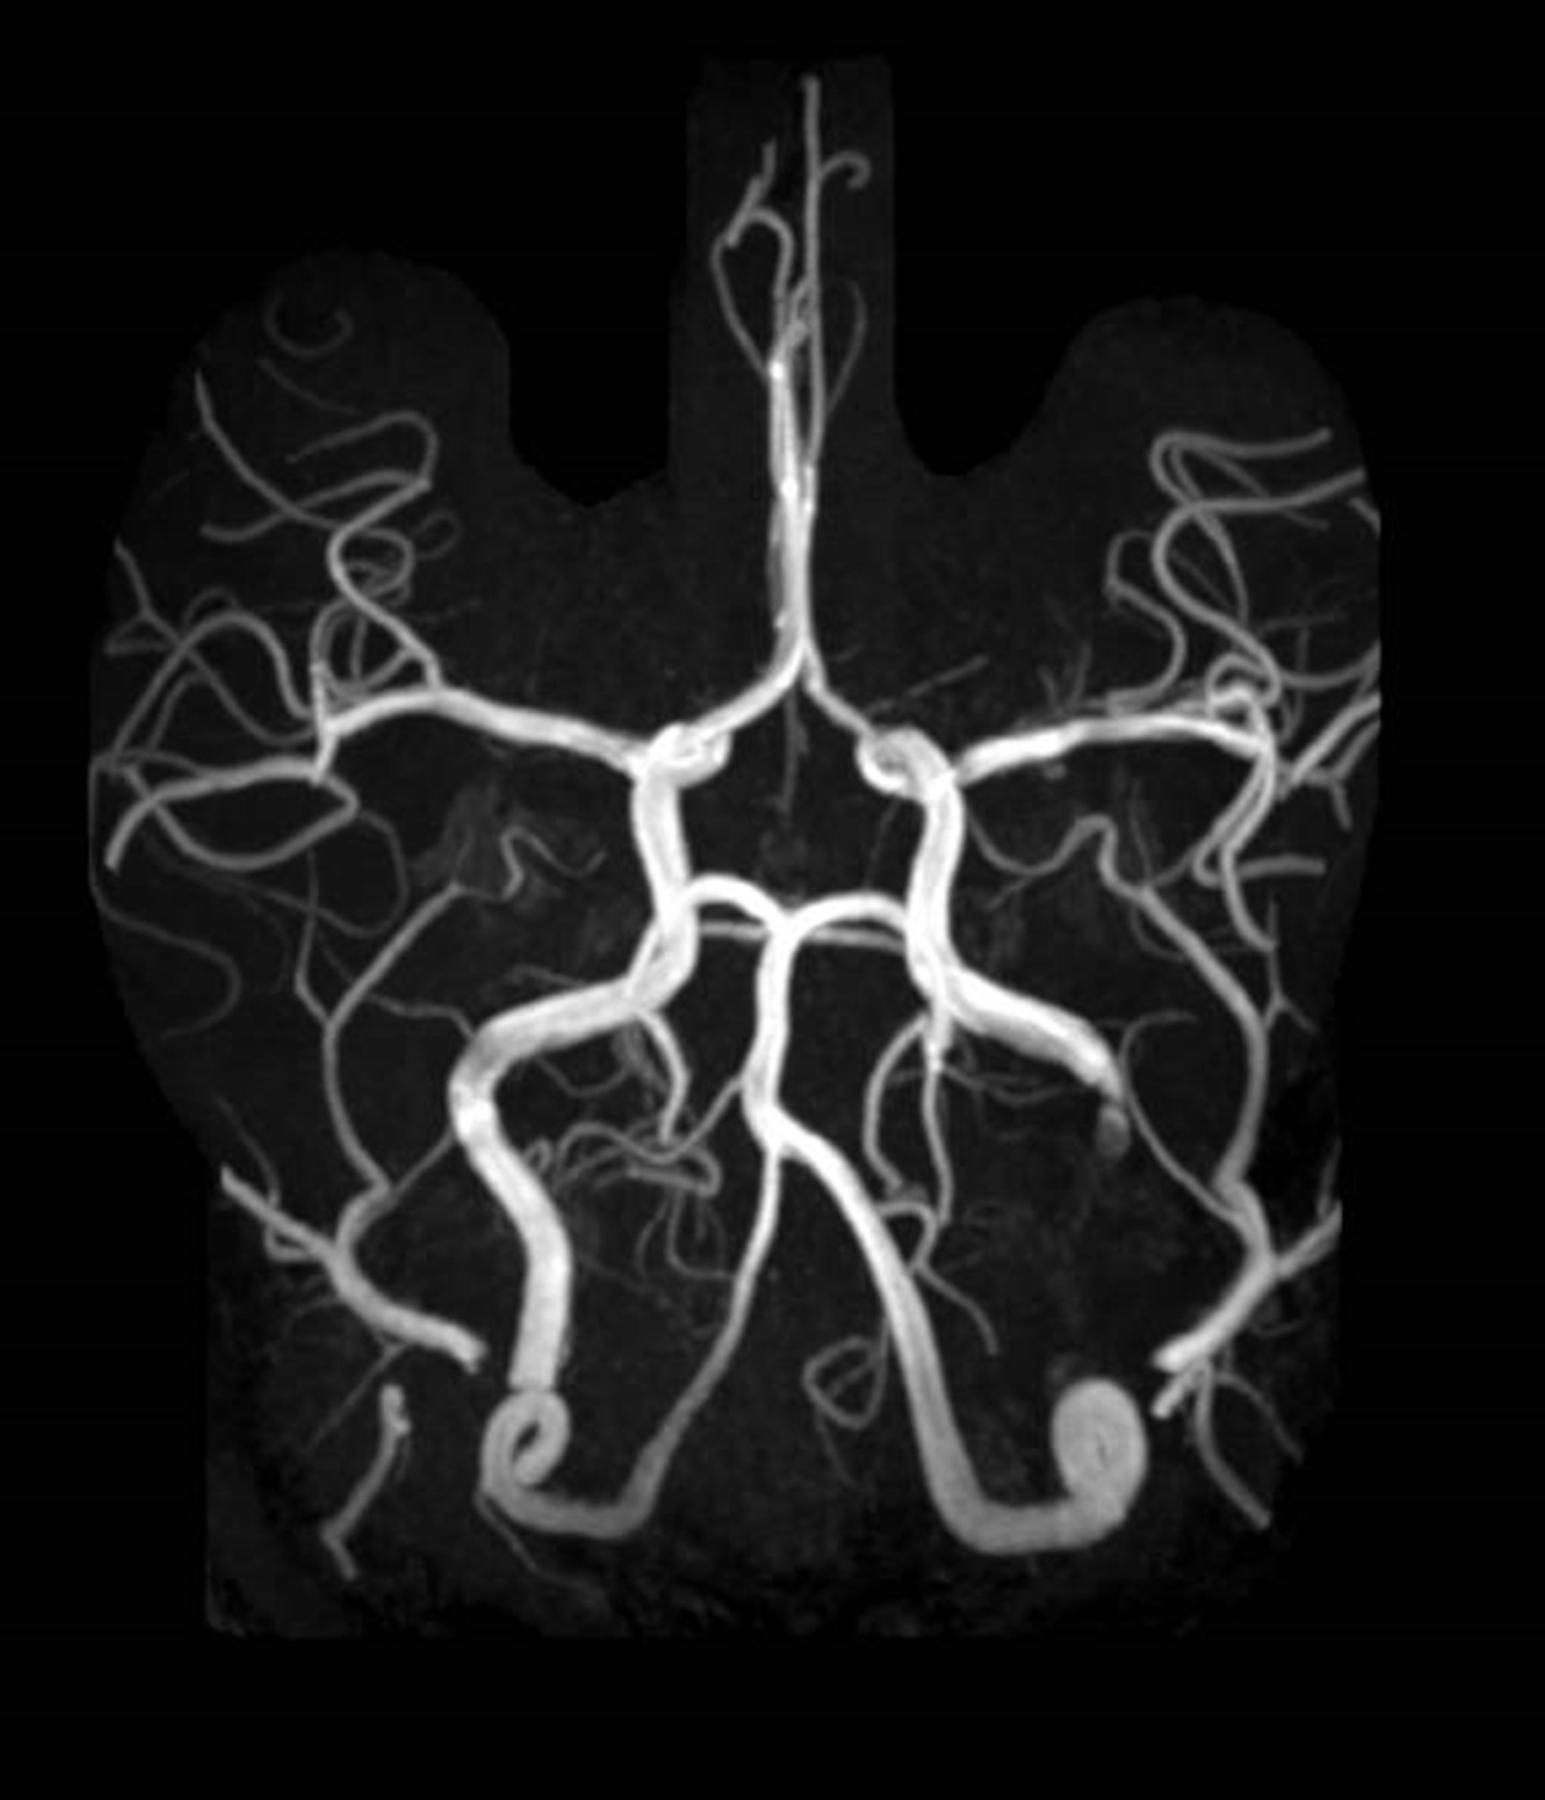

He was great: Dr. Leung has been amazing. He spent so much more time with me than any other doctor, but also much more time than I would have assumed he could spend with me. No one else had ever shown me the scans from the MRI or CT scans. He took me through each one of the scans and showed me where the previous stroke was. He explained every single thing from treatment options to making sure I understood why the stroke could have possibly could have happened.